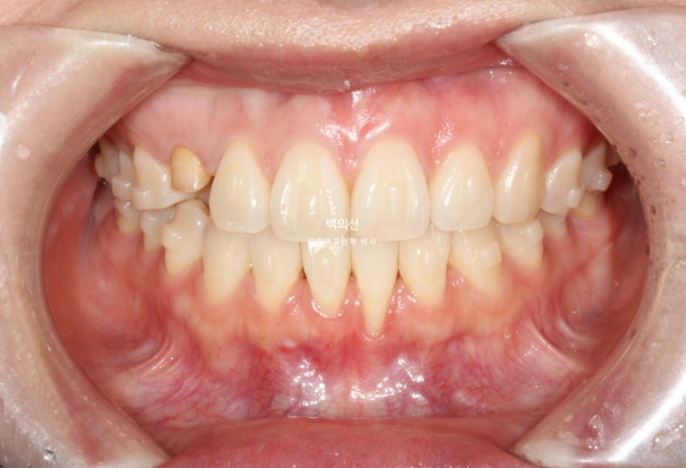

작년 가을 교정치료를 위해 내원한 환자분입니다.

오래 전 교정치료를 이미 받은 상태로 철사유지장치가 붙어있는 상태에서 오셨습니다.

아래 앞니 하나가 뿌리가 바깥으로 나가면서 잇몸퇴축이 심합니다.

잔존유치는 영구치 송곳니가 매복되는 바람에 남아있는 상태입니다.

잔존유치의 뿌리가 썩 튼튼하지는 않으나, 동요도는 전혀 없어 쓸때까지 쓰기로 합니다.

색이 어두운 치아는 잔존유치에 레진을 덮어놓은 상태이고 이번기회에 재교정을 하면서 이 치아도 변색된 레진을 제거하고 라미네이트든 크라운이든 깔끔하게 치료를 원하셨습니다.

오래 전 했던 교정으로 어금니 교합은 나쁘지 않은 상태입니다.